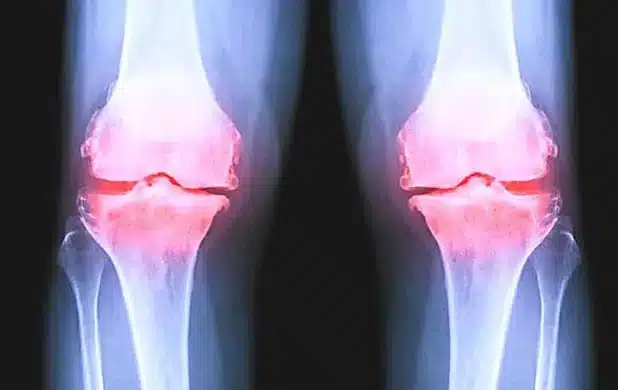

Na jaren van pijnlijke gewrichtsslijtage in mijn knieën, handen, heup en het uitproberen van talloze 'oplossingen', weet ik precies hoe slopend artrose kan zijn.

Want als je eenmaal last hebt van artrose in je knieën, handen of heup, wil je er alles aan doen om weer normaal te kunnen bewegen zonder die constante pijn en stijfheid...

En juist die chronische ontstekingsprocessen en kraakbeenafbraak in je knieën, handen, heup of andere gewrichten zorgen ervoor dat je klachten blijven terugkomen - omdat je lichaam in een constante staat van ontsteking en gewrichtsslijtage verkeert.

Uit recent onderzoek blijkt dat maar liefst 1,2 miljoen Nederlanders last heeft van artrose, en 70% van mensen boven de 65 heeft tekenen van gewrichtsslijtage.

Vooral artrose in knieën en handen komen het meest voor, gevolgd door heup artrose en schouder artrose.

Nog verontrustender: bij 75% van de mensen worden de klachten progressief erger als de onderliggende ontstekingsprocessen en kraakbeenafbraak niet worden aangepakt.